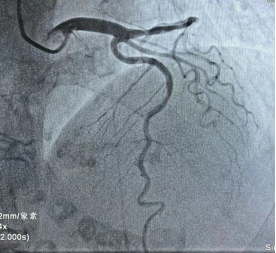

回旋支远端完全闭塞

此时,患者的胸痛症状丝毫没有缓解,复查心电图显示下壁导联ST段仍持续抬高。患者病情刻不容缓,经过短暂思考后,熊主任当机立断:尝试开通回旋支远端血管!在熊主任的指导下,刘燃医师小心翼翼的置入预扩球囊扩张回旋支远端,果然发现左旋支直径2.5mm,是右心供血功能血管。但是血管扩张后患者突然出现心率减慢、血压降低的现象,面对这种突发状况,熊主任考虑患者是再灌注后血管痉挛、心律失常,刘医生立即向冠脉内注射硝酸甘油200μg,随后患者心率、血压回升到正常。在进行重复造影后可见患者回旋支远段粗大且长,延伸至右心,再次确定回旋支远端为“罪犯血管”。经过球囊扩张手术后,血管狭窄解除,血流3级,心电图提示下壁导联明显回落,胸痛症状明显缓解,手术有效,抢救成功!